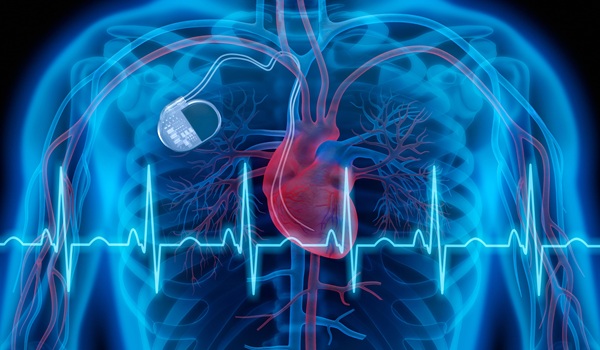

Nuevo enfoque de estimulación reduce complicaciones en pacientes con insuficiencia cardíaca

Sistema de ablación por campos pulsados agiliza los procedimientos de fibrilación auricular